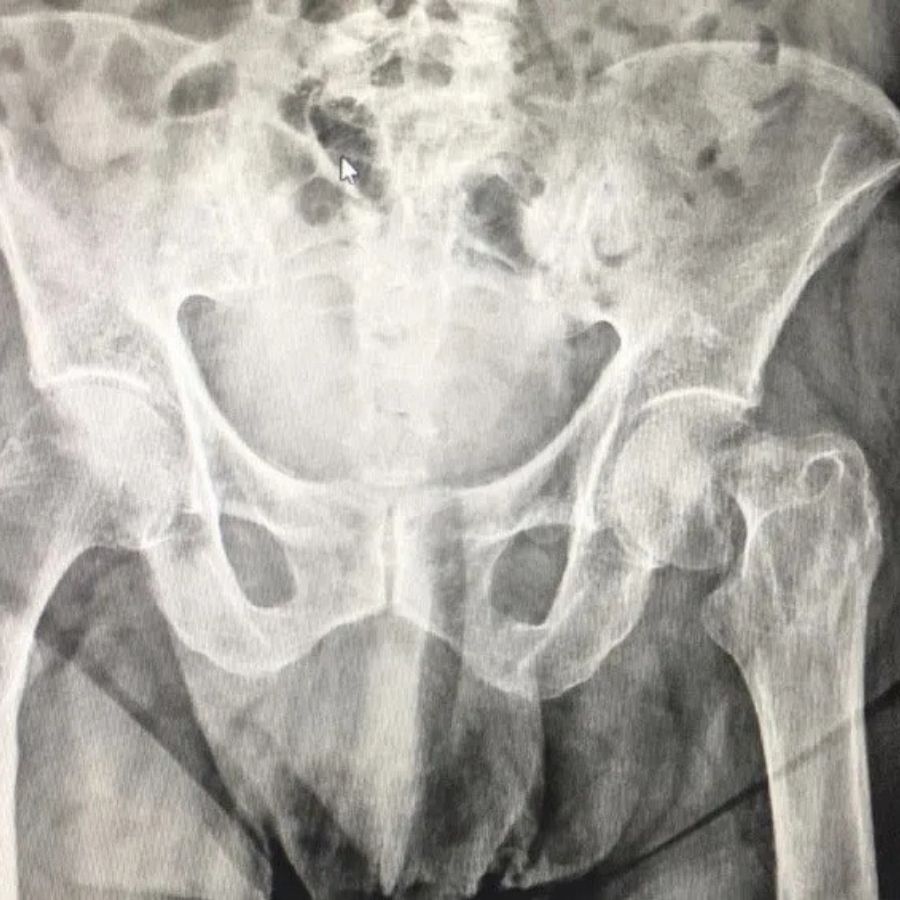

È un esperto nella Chirurgia Protesica del ginocchio e dell’anca, nelle tecniche di Artroscopia del Ginocchio, nella ricostruzione del legamento crociato anteriore e nelle plastiche di rinforzo esterne per le instabilità rotazionali del ginocchio. Altri interventi da lui eseguiti con frequenza sono il trattamento chirurgico delle fratture del piatto tibiale e del femore, trattamenti chirurgici per la lussazione della rotula. Tra i suoi campi d’interesse ci sono anche la Chirurgia Mini-Invasiva e la Traumatologia Sportiva. Da qualche anno è interessato all’applicazione di PRP per il trattamento di malattie acute e croniche dei tendini e delle articolazioni. Attualmente è Chirurgo Ortopedico presso la Clinica Fornaca di Sessant, Dirigente Medico di I livello presso l’Ospedale Humanitas Gradenigo e svolge la libera professione presso il suo studio privato a Torino.